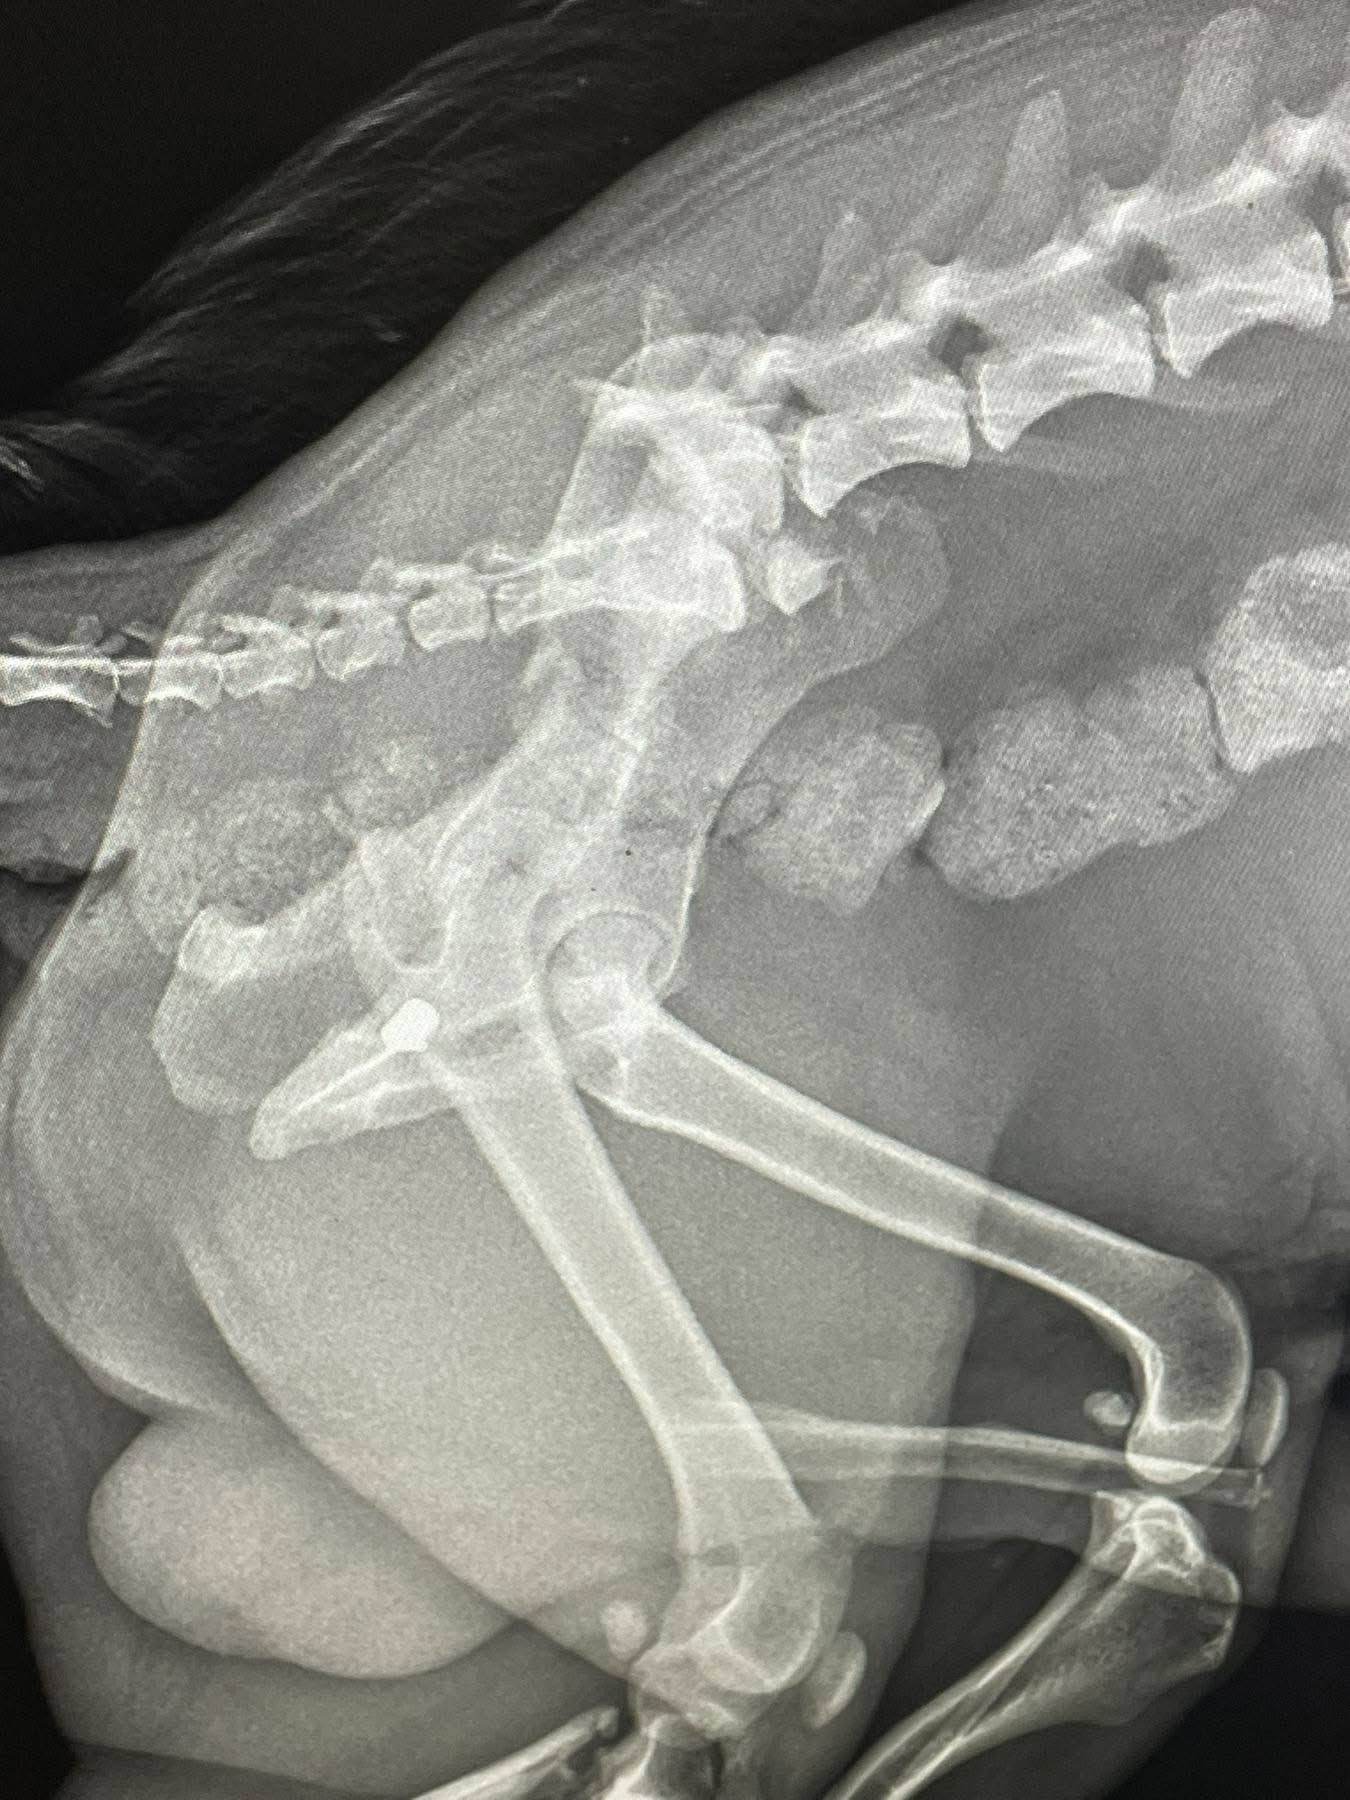

Під час моніторингу соціальних мереж правоохоронці виявили публікацію про поранену собаку, яку знайшли на одній із вулиць міста. Згідно з інформацією волонтерів, після огляду та рентгену у тілі тварини виявили дві кулі, а також роздроблені кістки лапи. Поліція зареєструвала подію та розпочала перевірку. Наразі тривають слідчі дії для встановлення обставин інциденту та осіб, які можуть бути причетними до стрілянини по собаці. Правоохоронці просять усіх небайдужих, які допомагали пораненій тварині або володіють будь-якою інформацією про подію, звернутися до Мукачівського районного управління поліції.